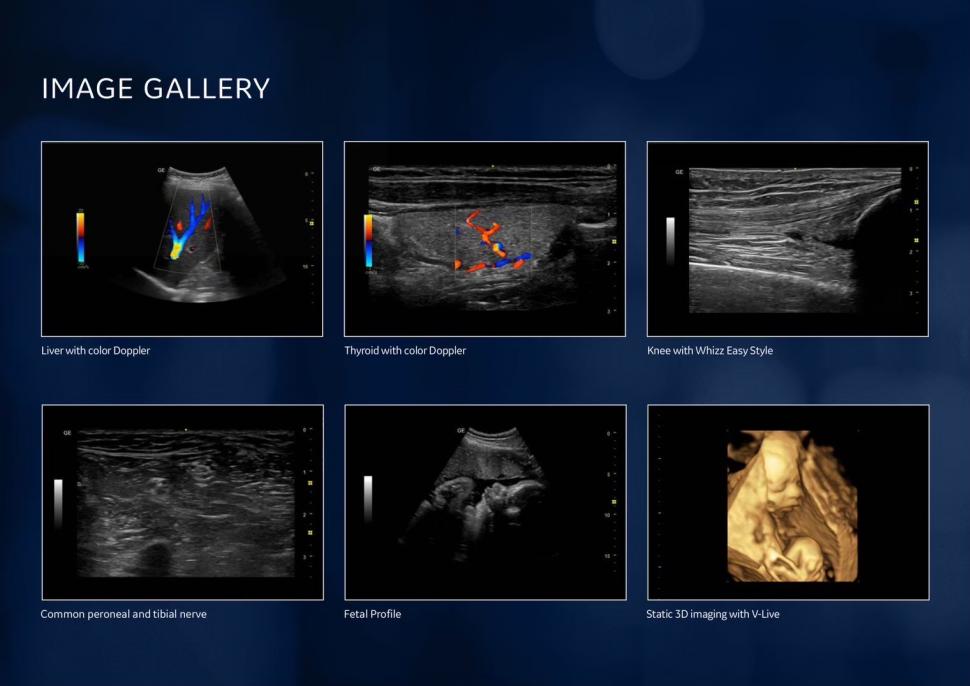

ชื่อเครื่อง

Versana Premier™ R2 เป็นเครื่องอัลตราซาวด์ (Ultrasound System) รุ่นพรีเมียมจากตระกูล Versana

คุณสมบัติเด่น

• พลังและความหลากหลาย: ใช้งานได้ครอบคลุมทั้งศูนย์วินิจฉัยโรค (imaging center), คลินิกทั่วไป, คลินิกเฉพาะทาง, คลินิกครอบครัว และโรงพยาบาล

• คุณภาพสูงและแม่นยำ: ผลิตภาพคุณภาพสูงอย่างสม่ำเสมอ ทั้งวันต่อวัน ผู้ป่วยต่อผู้ป่วย เพื่อช่วยให้วินิจฉัยได้อย่างแม่นยำ

• รองรับการตรวจที่หลากหลาย:

• Abdominal (ช่องท้อง)

• OB/GYN (สูติ-นรีเวช)

• Cardiac (หัวใจ)

• Small Parts (อวัยวะขนาดเล็ก เช่น ต่อมไทรอยด์)

• Urology (ทางเดินปัสสาวะ)

• Vascular (หลอดเลือด)

• Musculoskeletal (กล้ามเนื้อและกระดูก)

• Pediatric (กุมารเวช)

จุดเด่นเพิ่มเติม

• ถูกออกแบบมาเพื่อ ความอุ่นใจ (peace of mind) ของแพทย์และผู้ป่วย

• สามารถทำรายงานได้อย่าง ทันท่วงทีและแม่นยำ ส่งต่อให้แพทย์เจ้าของไข้และแพทย์ที่ส่งตรวจ